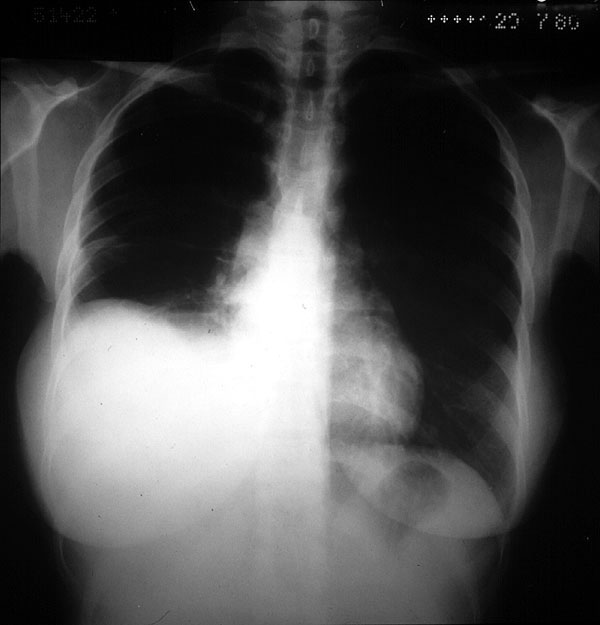

Placa 44